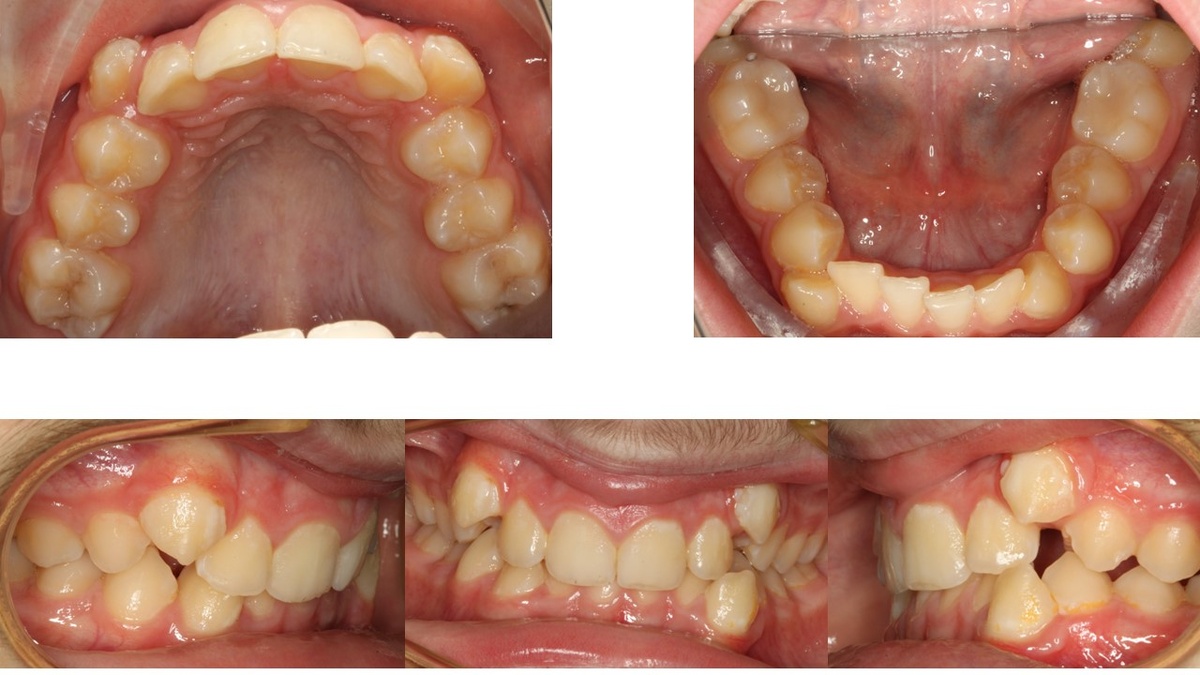

Вот такой пациент обратился к нам 7 лет назад

Сильно неровные зубы и сильно плохая гигиена!

Наверху миллиметров 10 не хватает!

Внизу где-то 8 мм!